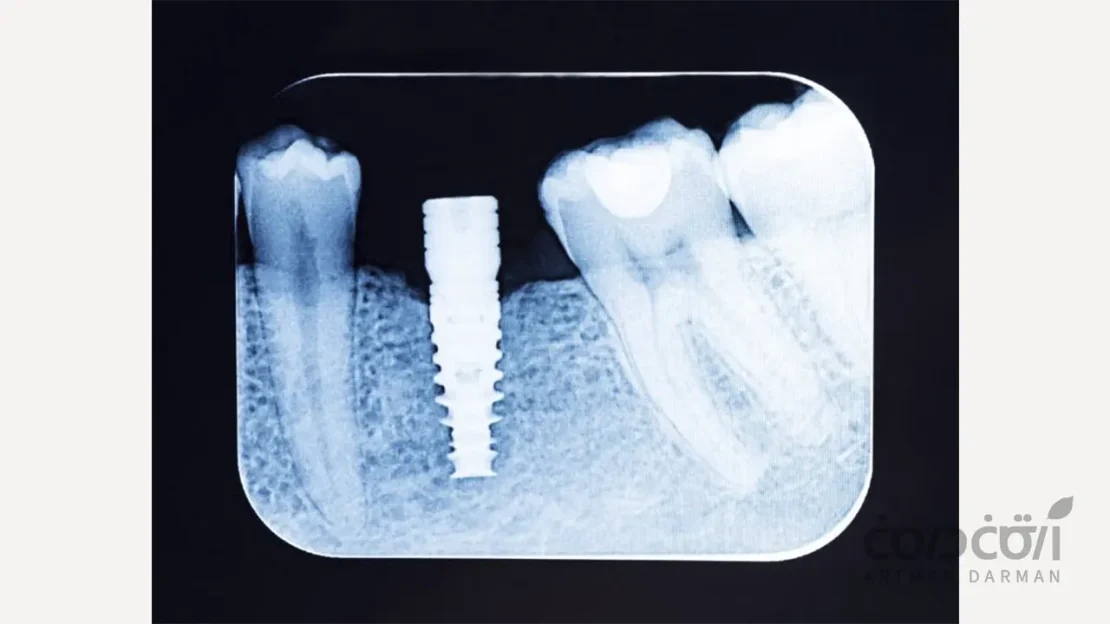

یکی از بزرگترین نگرانی ها در فرآیند درمان ایمپلنت، دوره انتظار چند ماهه برای جوش خوردن پایه تیتانیومی به استخوان فک است. این دوره که از نظر علمی “اوسئواینتگریشن” نامیده میشود، برای بسیاری از افراد طولانی و خستهکننده به نظر می رسد. بنابراین این سوال که آیا راهی برای دستیابی به جوش خوردن سریع ایمپلنت دندان وجود دارد، یک پرسش کاملاً منطقی و به جاست. در این مقاله هرچیزی که میبایست در این خصوص بدانید را توضیح می دهیم.

اوسئواینتگریشن یا یکپارچگی استخوانی، یک فرآیند بیولوژیک است که طی آن، سلول های استخوان ساز بدن به طور مستقیم به سطح تیتانیومی ایمپلنت متصل شده و آن را به جزئی ثابت و پایدار از فک تبدیل می کنند. این یک فرآیند طبیعی است که بدن برای ترمیم زخم استخوانی (حفره ایجاد شده برای ایمپلنت) طی می کند و مانند هر فرآیند بیولوژیک دیگری، به زمان نیاز دارد.